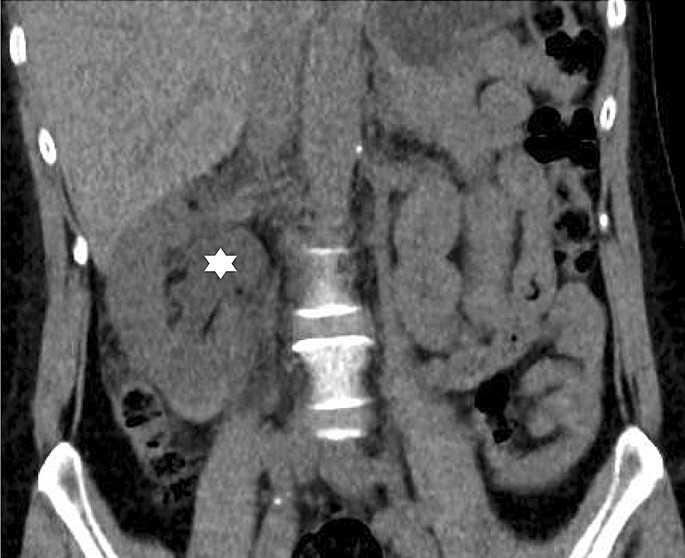

9/ Chronic hypertension due to the "Page kidney"

Pressure-induced ischemia from a large subcapsular hematoma → activation of RAS→ HTN

radiopaedia.org/articles/page-…

pubmed.ncbi.nlm.nih.gov/1951341/